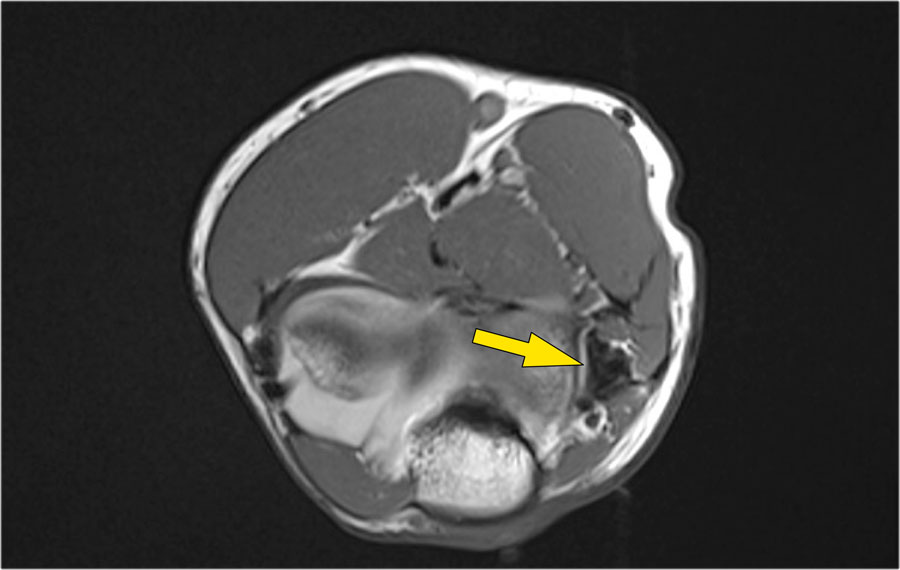

Khi quan sát trên lát cắt ngang (axial), chúng ta có thể nhận thấy sự hình thành gai xương khổng lồ.

Lưu ý rằng dây thần kinh trụ (mũi tên màu xanh) nằm cạnh các gai xương này và những bệnh nhân này có thể biểu hiện bệnh lý thần kinh trụ.